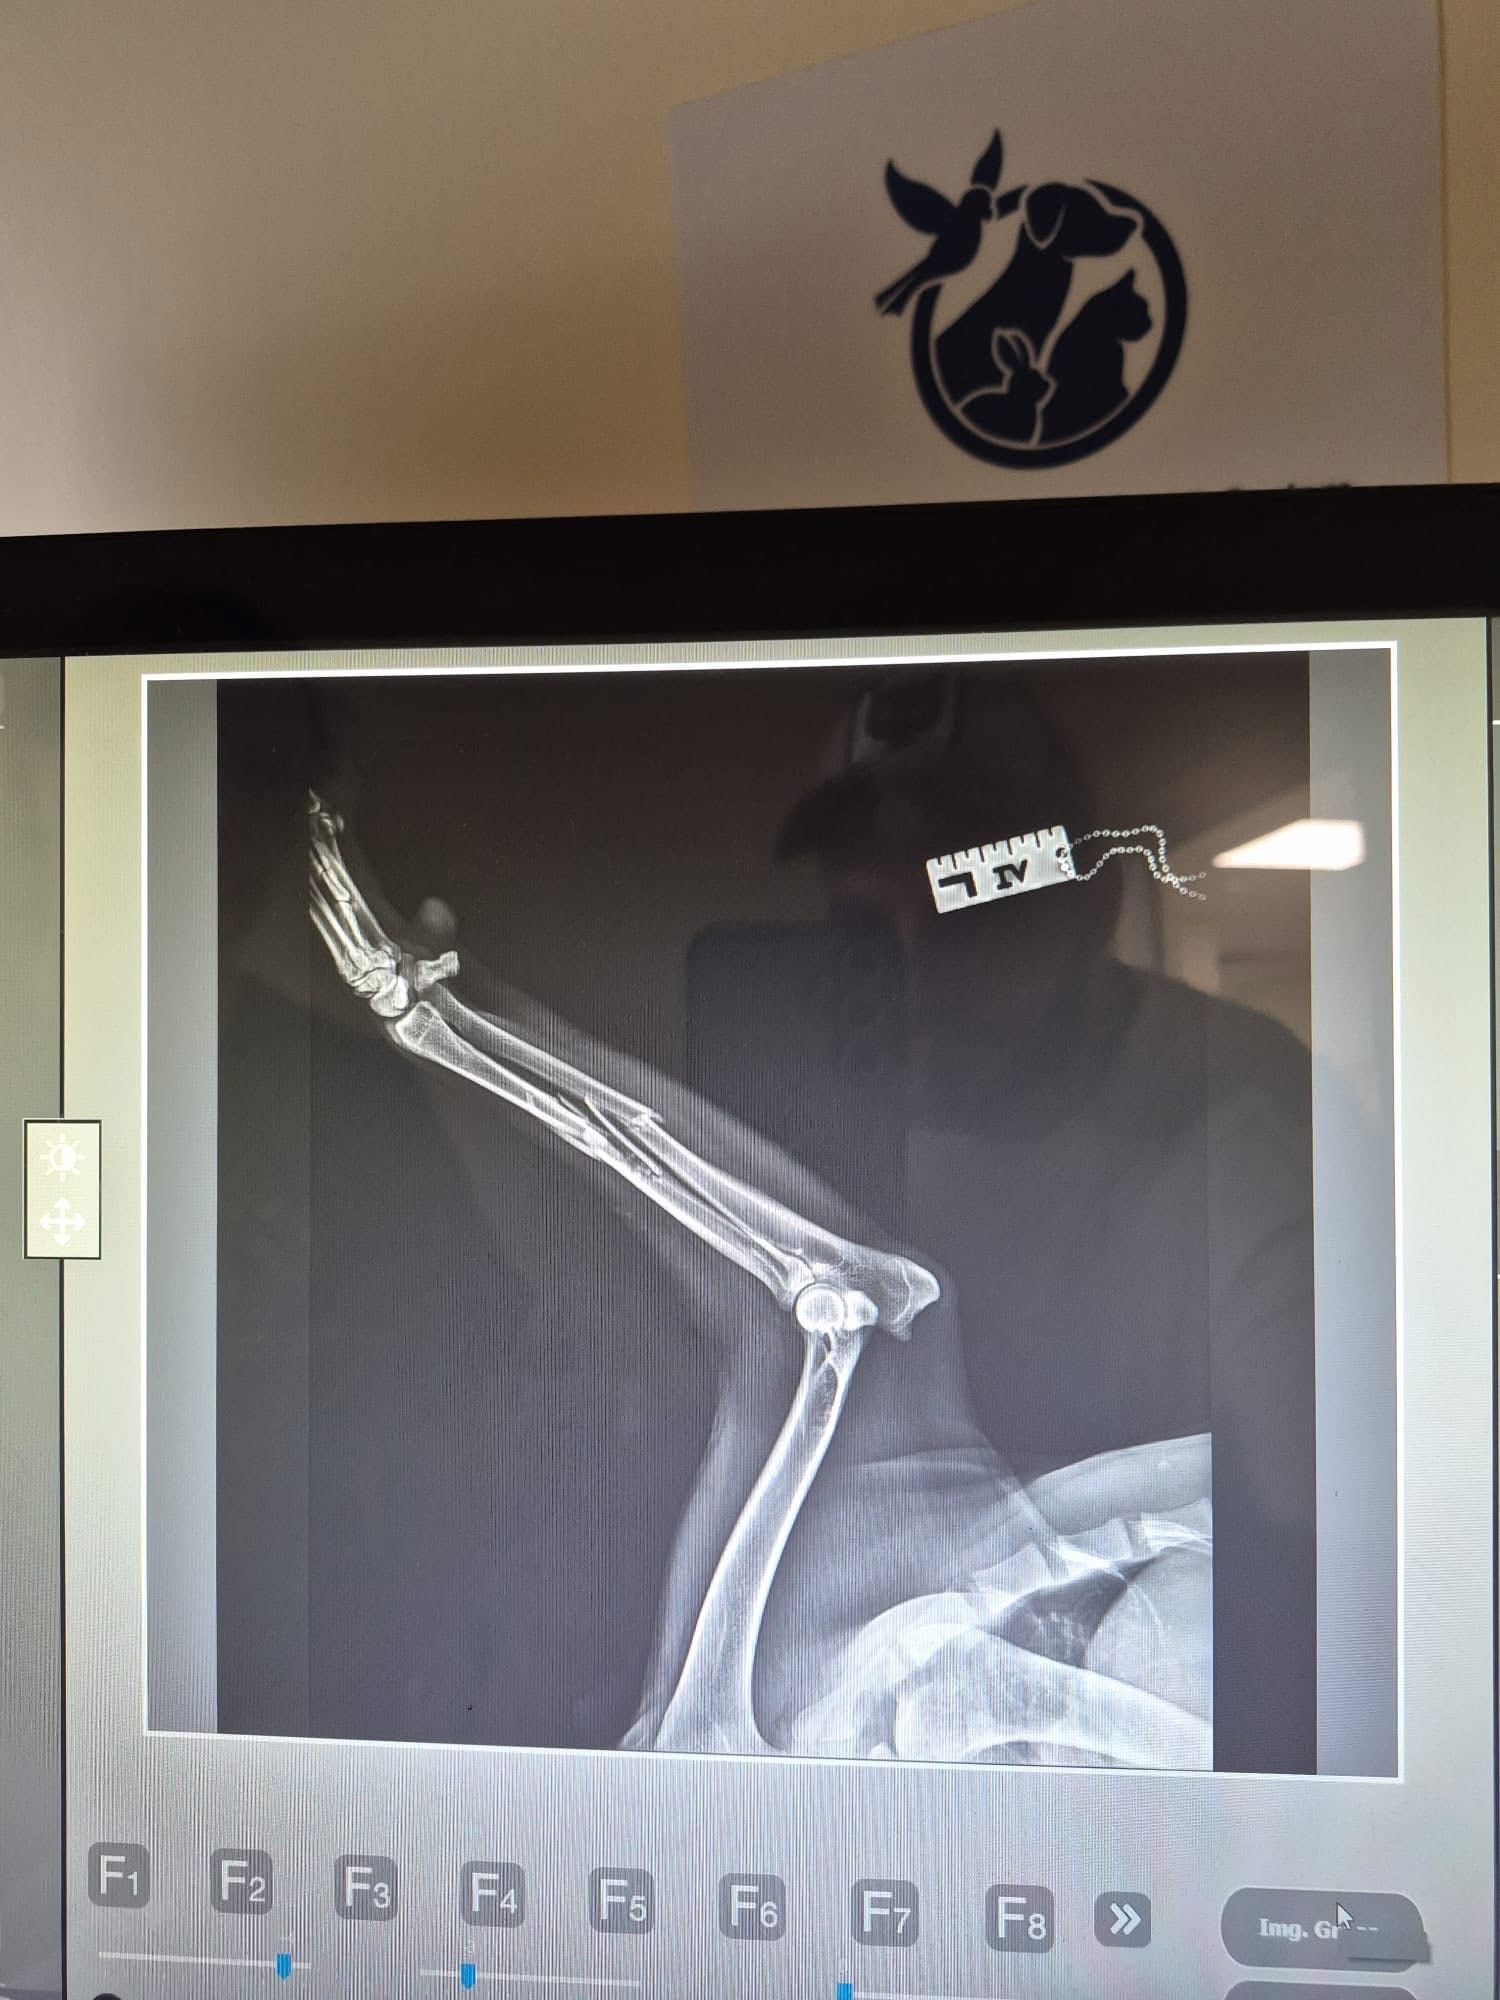

‼️ CÂINELE, VICTIMĂ NEVINOVATĂ – CU OASELE RUPTE ȘI DURERE ÎN OCHI

Animalul a fost găsit cu multiple fracturi, într-o stare critică. A fost preluat de echipa Protecției Animalelor CJ Ilfov, iar medicul veterinar Aurelian Ștefan și echipa sa au reușit, cu eforturi uriașe, să-i salveze viața. În prezent, câinele se află într-un sistem de foster, la o familie iubitoare.